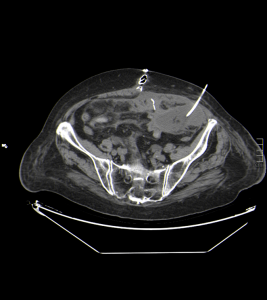

Se realiza procedimiento quirúrgico resolutivo de la obstrucción intestinal, y se procede a colocar drenaje con pig-tail para evacuar el absceso peritoneal izquierdo encontrado en las imagenes de control:

Haz click en las imágenes para verlas ampliadas